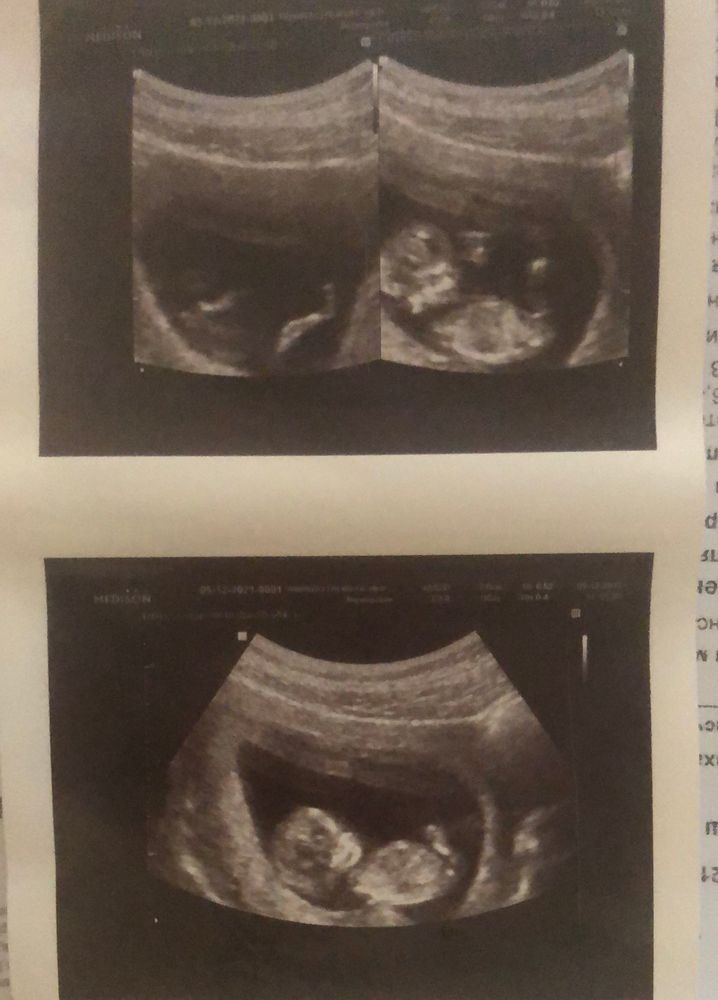

1 Скрининг на 11,5 недель 😄

У нас получилось! Я беременна!Была на первом скрининге , это волшебство 🧙 но самое смешное как мой малыш показал свой пол …Девочки в жизни такое не видела , настолько четко было видно что мы с врачом в шоке были 🤦🏻♀️😄 причём врач мне не говорил , а я увидела и офигела …. Вот удивляешь как у такой маленькой крохи все видно 😄

но на фото скрининга Малыш выглядит как из фильма «Чужой»😂 Особенно сверху правая фотка

я вот думаю у меня только так или у многих ,а то у некоторых смотрю такие мимишки 😃

Малыш просто чудо❤ очень хорошо видно его на нижней фотографии🥰 растите большие, крепкие и здоровенькие🙏💕